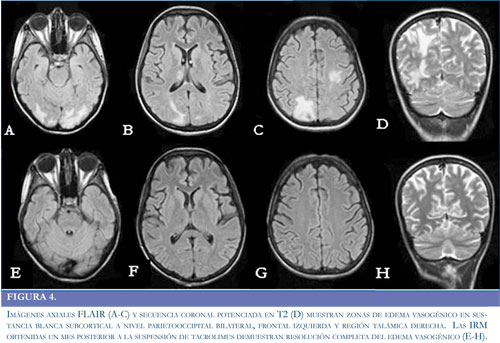

Paciente de 24 años de edad previamente sana, sin antecedentes médicos de importancia, quien ingresó a la institución por sintomatología de 20 días de evolución, consistente en fiebre no cuantificada asociada a disnea progresiva de medianos hasta pequeños esfuerzos y edema de miembros inferiores en los últimos dos días. Intra-hospitalariamente evolucionó con deterioro de la función sistólica y derrame pericárdico que aumentó progresivamente. Durante la estancia en la Unidad de Cuidados Intensivos (UCI), la paciente presentó hipotensión, inestabilidad hemodinámica, necesidad de soporte vasopresor y requirió reanimación cardiopulmonar y asistencia ventricular izquierda. Se confirmó diagnóstico de miocardiopatía chagásica aguda y se llevo a trasplante cardíaco ortotópico de urgencia, iniciándose medicación inmunosupresora con corticoides, basiliximab y micofenolato, como parte del manejo del paciente trasplantado. El inicio del tacrolimus se realizo de forma tardía (1 mes después del trasplante), debido a previa falla renal que requirió hemodiálisis. Permaneció un mes en UCI al cabo del cual y sin compromiso neurológico previó, inicio somnolencia sin una causa aparente, por lo que se decidió realizar una tomografía computada simple (TC) de cráneo, sin observar anormalidades (Figura 2A-2B). Tras presentar mejoría clínica, fue trasladada al servicio de hospitalización general. Dos días después del traslado manifestó cefalea global intensa asociada a irritabilidad, ansiedad y elevación de las cifras tensionales con un difícil control de las mismas (Figura 3). Posteriormente presentó dos episodios convulsivos tónico-clónicos generalizados de 2 minutos de duración con desviación de la mirada a la izquierda, los cuales cedieron a la administración de midazolam e infusión de fenitoína. Los paraclínicos, incluidos electrolitos y pruebas de función hepática, renal y el análisis del LCR se encontraron dentro de parámetros normales. Se realizó una nueva TC de cráneo en la que se observaron hipodensidades de la sustancia blanca comprometiendo regiones occipito-parietales bilaterales y región talámica derecha (Figura 2C-2D). Las imágenes por Resonancia Magnética (IRM) confirmaron el compromiso de la sustancia blanca con lesiones hiperintensas en las secuencias T2 y FLAIR a nivel frontal, parietal y occipital bilaterales, así como en región talámica derecha, considerando cuadro compatible con SEPR (Figura 4A-4D). Adicionalmente se realizó medición de niveles plasmáticos de tacrolimus, encontrando marcado aumento de los mismos. Se suspendió la administración de eritropoyetina y se realizó cambio de tacrolimus a everolimus y se ajustaron las dosis de prednisolona. Después de las primeras 24 horas tras realizar estos cambios presentó recuperación de su estado de conciencia y resolución de su cuadro clínico, sin nuevos episodios convulsivos, ni otras manifestaciones neurológicas. La RM cerebral realizada un mes después del deterioro neurológico, mostró una resolución completa del compromiso de la sustancia blanca posterior (Figura 4D-4G).

Las manifestaciones clínicas más frecuentemente descritas en el SEPR, corresponden a deterioro del estado de conciencia, cefalea, episodios convulsivos y alteraciones visuales (31). Todas estas manifestaciones se han descrito independientemente del factor precipitante. Los episodios convulsivos corresponden principalmente a crisis parciales complejas, aunque también se han descrito crisis tónico clónico generalizadas (32). La alteración visual más común es la ceguera cortical, seguida de otras manifestaciones como hemianopsias, negligencia de campos visuales y visión borrosa (33). En el caso descrito la paciente presentó un rápido deterioro del estado de conciencia, cefalea y crisis convulsivas, sin evidencia de alteraciones visuales, posiblemente por el rápido compromiso de la conciencia. La otra característica fundamental del SEPR corresponde a los cambios en las neuroimágenes, dados por alteraciones predominantes de la sustancia blanca subcortical, especialmente en los lóbulos temporales, parietales y occipitales, generadas por edema cerebral vasogénico (1). La RM cerebral se ha convertido en el examen de elección en la evaluación de estas lesiones (34). En la secuencia T2 de la MR se observa incremento en la intensidad de la señal en las áreas lesionadas. La secuencia FLAIR permite una mejor visualización de las alteraciones en la sustancia blanca, además de una mejor identificación de las lesiones supratentoriales.